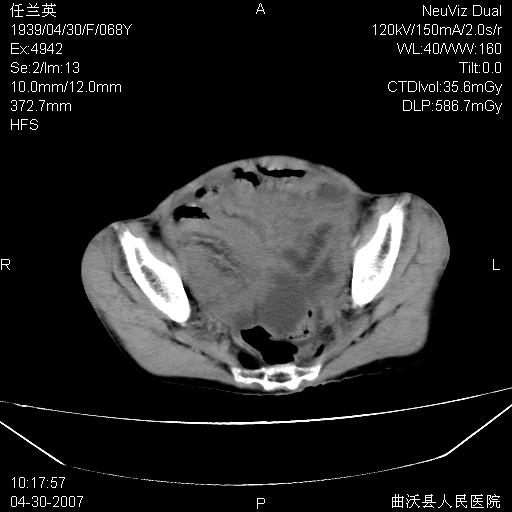

患者,女,68岁,感觉腹部憋涨发硬数天,查b超发现左盆腔有囊性肿物和少量腹水,行ct检查

1.考虑卵巢肿瘤并腹腔广泛性转移可能性大;

2.腹盆腔少量积液。

支持左侧卵巢恶性肿瘤伴网膜、腹膜广泛转移。

难的一见 典型 - 网膜饼  冰冻骨盆 可以当教学片了